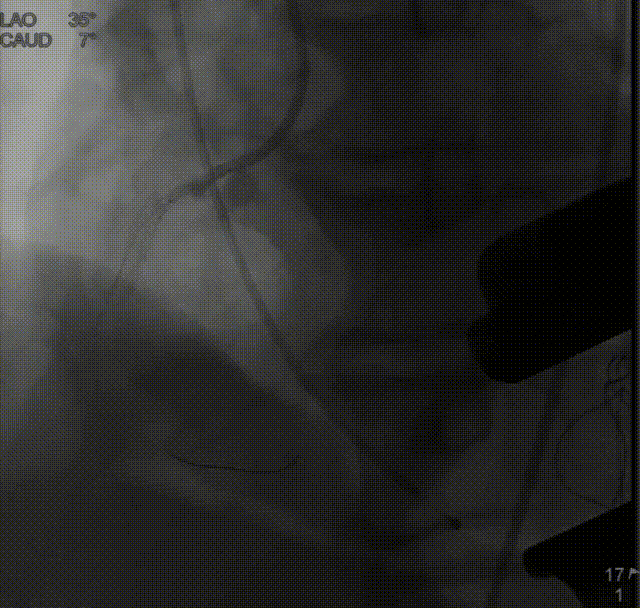

右冠造影,显示近段重度狭窄:

左冠造影未见明显狭窄:

于右冠植入冠脉支架一枚,冠脉血流通畅:

定位件入窦后造影:

降落瓣膜件:

140bpm快速起搏下释放瓣膜:

复查根部造影,未见明显反流:

食道超声瓣架位置正确,启闭良好,未见明显瓣周漏: